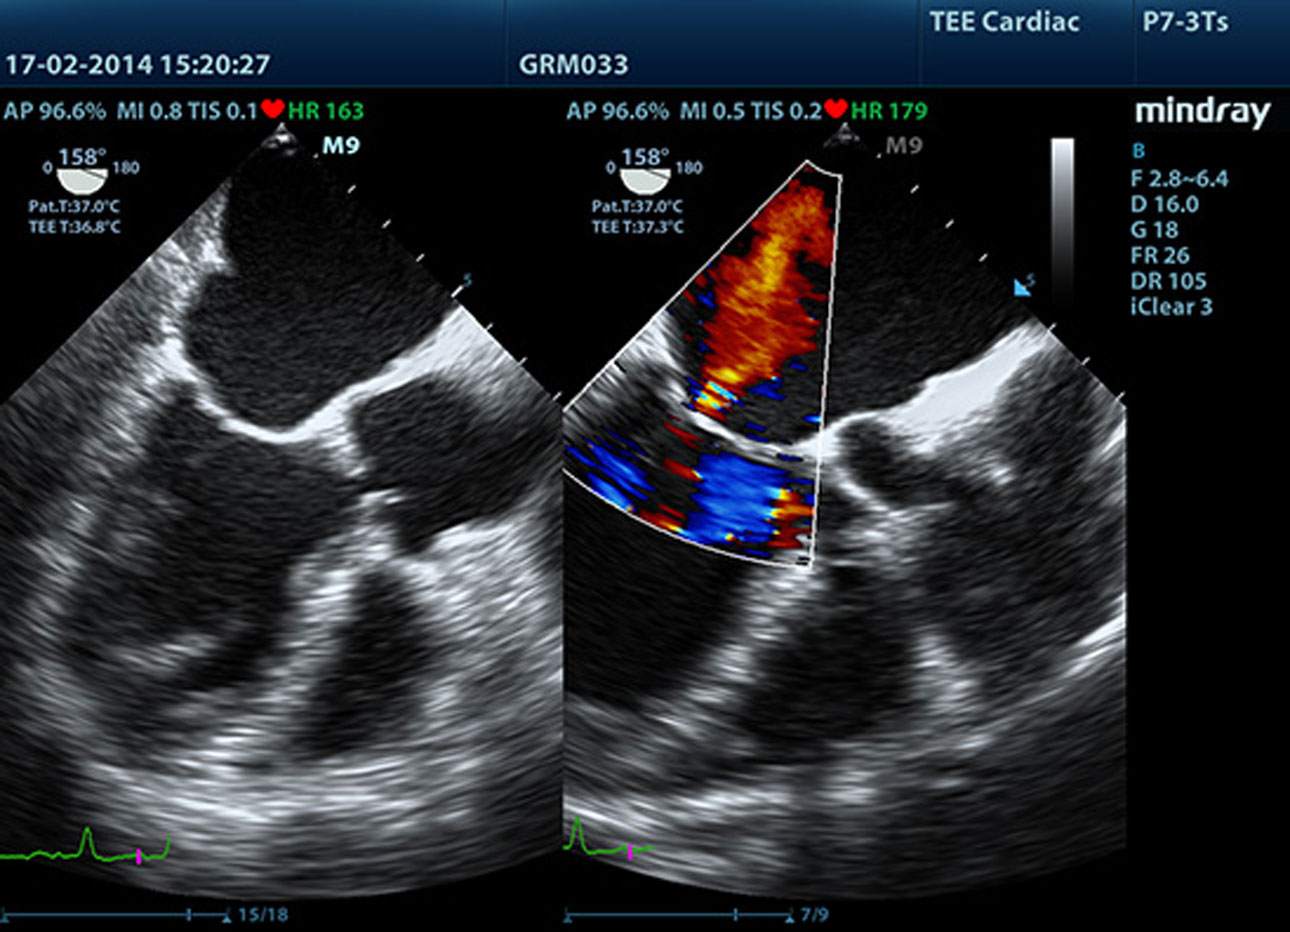

Fracci├│n de eyecci├│n autom├Ītica (AutoEF)

Una forma inteligente de analizar las 2D para reconocer autom├Īticamente los niveles diast├│licos/sist├│licos y generar la estimaci├│n diast├│lica, el volumen diast├│lico, la fracci├│n de eyecci├│n (EDV/ESV/EF), etc. resultantes del m├®todo Simpson.